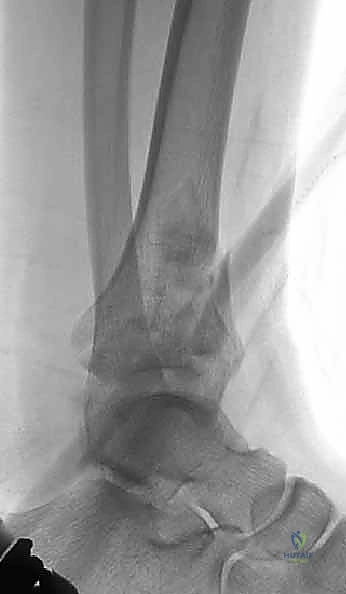

1. التصوير بالأشعة السينية التقليدية (X-Rays)

يتم أخذ صور من ثلاث زوايا (أمامية خلفية AP، جانبية Lateral، ومورتيس Mortise). تعطي هذه الصور فكرة عامة عن نمط الكسر، قصر الساق، ومدى انزياح العظام.

تصنيف كسور البيلون

يعتمد الأطباء على أنظمة تصنيف عالمية لتوحيد لغة التواصل وتحديد خطة العلاج:

* تصنيف رويدي وألجاور (Rüedi and Allgöwer):

* النوع الأول: كسر مفصلي بدون انزياح.

* النوع الثاني: كسر مفصلي مع انزياح، لكن دون تفتت شديد.

* النوع الثالث: كسر مفصلي مع انزياح وتفتت شديد (انفجار المفصل).

* تصنيف AO/OTA: وهو التصنيف الأشمل الذي يقسم الكسور إلى أنواع A (خارج المفصل)، B (مفصلي جزئي)، و C (مفصلي كامل ومعقد).